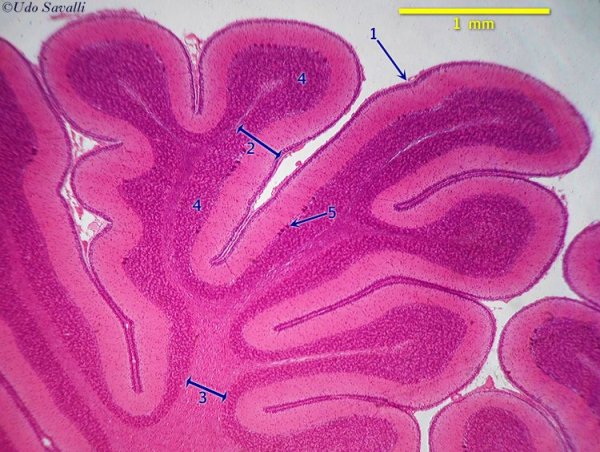

Мозжечок - это часть головного мозга, отвечающая за координацию движений и поддержание равновесия. В его структуре выделяются белое и серое вещество. Белое вещество состоит из нервных волокон, которые передают сигналы между различными частями мозга. Серое вещество содержит клетки - нейроны, выполняющие функцию обработки информации. На картинках гистологического среза мозжечка можно увидеть какие-то детали его структуры, такие как пуркиневские клетки или черный вещества, что помогает лучше понять организацию этой важной части мозга.

Мозжечок гистология препарат

Мозжечок гистологический препарат